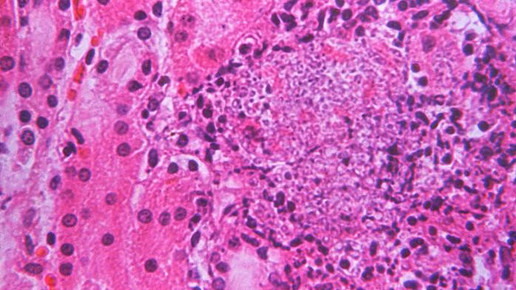

Candida

Ein neuer Hefepilz treibt auf der Welt sein Unwesen. Auch in Deutschland wurde der erstmals 2009 nachgewiesene Erreger bereits gefunden. Zwar steigt die Zahl bekannter Fälle – insgesamt aber sind es nur wenige.

In Deutschland werden immer mehr Fälle bekannt, in denen schwer kranke Patienten mit dem gefährlichen Hefepilz Candida auris infiziert sind. „Wir wissen von insgesamt sieben Patienten, die Candida auris hatten. Davon sind fünf aus dem vergangenen Jahr“, sagte Oliver Kurzai vom Nationalen Referenzzentrum für invasive Pilzinfektionen mit Sitz in Jena. Wegen des Hefepilzes gestorben sei hierzulande noch niemand. „Bei den Patienten, von denen wir es wissen, gibt es keine durch die Infektion bedingten Todesfälle“, sagte Zentrumsleiter Kurzai vom Lehrstuhl für Medizinische Mikrobiologie und Mykologie der Universität Würzburg.

2015 war der Hefepilz erstmals bei zwei Patienten in Deutschland gefunden worden. „Alle Fälle traten bislang in unterschiedlichen Krankenhäusern auf. Es sind soweit wir wissen Einzelfälle“, so Kurzai. Die zwischen 1950 und 2002 geborenen Männer und Frauen hatten nur gemeinsam, dass sie alle schwer krank waren. „Das sind Patienten, die zum Teil mit schwersten Grunderkrankungen im Krankenhaus sind.“

Der Hefepilz war 2009 in Asien erstmals nachgewiesen worden. Seitdem breitet er sich rasend schnell in der Welt aus. Zuletzt wurden in den USA, Großbritannien und Indien zahlreiche Erkrankungen erfasst. Kurzai geht davon aus, dass die Fallzahlen auch in Deutschland weiter steigen werden. „Das Risiko sehe ich als relativ erheblich an. Aufgrund der immer weiter zunehmenden globalen Mobilität breiten sich solche Erreger schnell aus. Es ist deshalb nur eine Frage der Zeit, bis wir ihn häufiger in Deutschland sehen. Anlass zu großer Sorge sieht der Experte nicht.

„Es ist eine bedrohliche Krankheit und wir wissen nicht genau, wie wir sie behandeln müssen. Aber es ist nicht Ebola“, sagte Kurzai. In Deutschland sei der Pilz, der in allen Fällen mit hoher Wahrscheinlichkeit von den Patienten aus anderen Ländern mitgebracht worden war, noch nicht weiterverbreitet worden.

Der Hefepilz ist gegen viele Anti-Pilz-Mittel resistent. Dennoch können betroffene Patienten mit vorhandenen Medikamenten behandelt werden. „Man muss ein bisschen gucken, aber es ist nicht so, dass wir mit dem Rücken zur Wand stehen“, sagt Kurzai. Für einen gesunden Menschen ist der Pilz keine Bedrohung. Candida auris kann zu Blutvergiftungen sowie Harnwegs- und Wundinfektionen führen.

Spezielle Symptome für den Pilz sind Kurzai zufolge noch nicht erfasst, er kann deshalb nur im Labor identifiziert werden. Der Hefepilz ist noch nicht meldepflichtig. Kurzai und sein Team hoffen dennoch, dass Kliniken und Labore Verdachtsfälle zur Auswertung an das Referenzzentrum schicken.